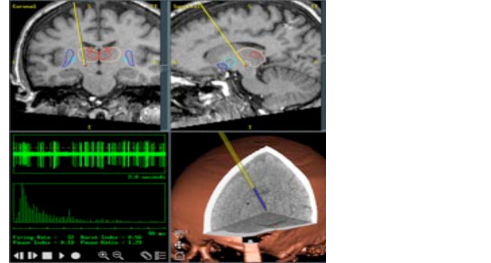

Lo scopo della terapia chirurgica è quello di riportare un equilibrio all’interno del circuito dei Nuclei della Base inibendo i neuroni del Nucleo Subtalamico mediante una stimolazione ad alta frequenza (Figura 6).

Questo avviene generando un campo elettromagnetico che genera impulsi ad una frequenza superiore ai 130 Hz. Il campo elettromagnetico viene generato da due elettrodi (uno per lato), che hanno le dimensioni di un filo di spago.

L’intervento dura dalle 5 alle 8 ore e avviene con il paziente sveglio. Questa circostanza, accettabile in quanto l’intervento non è doloroso, è resa necessaria dal fatto che durante l’intervento viene controllata la corretta collocazione degli elettrodi verificando al momento l’efficacia della stimolazione sulla rigidità muscolare e l’assenza di effetti collaterali. Una volta collocati a livello dei Nuclei Subtalamici, gli elettrodi vengono collegati ad una batteria, posta sotto la cute dell’area sottoclavicolare (Figura 7).